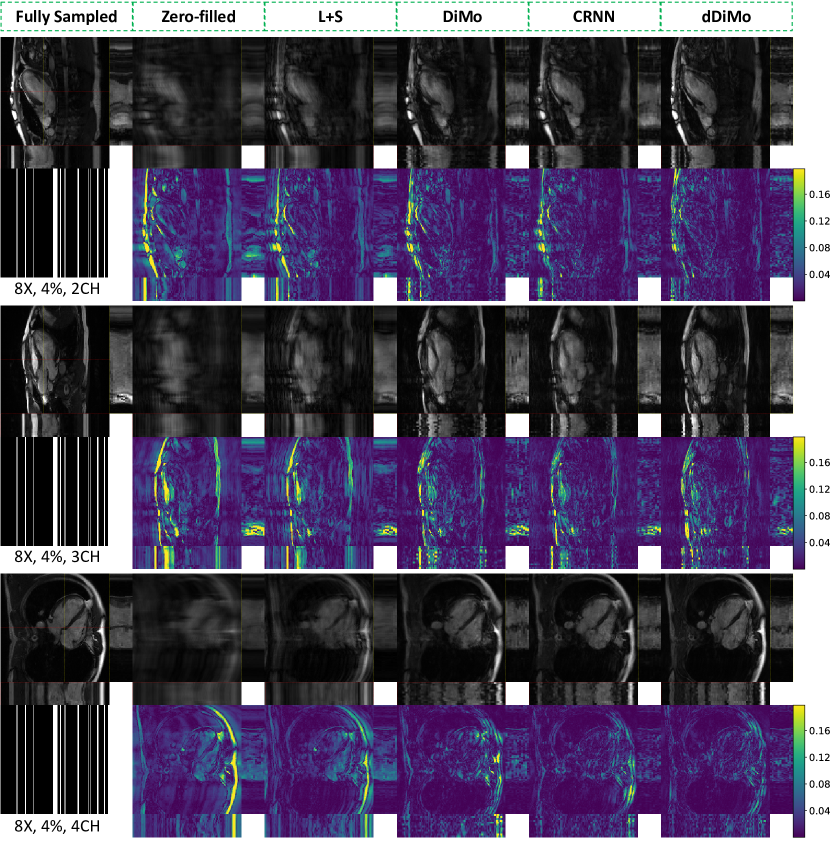

4.1 Results of Cardiac Cine

Exemplary reconstructions from various methods for cine images at different acceleration factors and cardiac views are shown in Figure 4, Figure 5, and Supporting Information Figure S1 and Figure S2. The proposed dDiMo method demonstrates superior performance in artifact suppression, detail preservation, and accurate cardiac motion capture, producing sharp and clear reconstructions. In contrast, competing methods, including L+S, DiMo, and CRNN, exhibit notable artifacts, spatial blurring, and temporal misalignment, particularly at higher acceleration factors. Exemplary - profiles extracted along the vertical yellow dashed line and horizontal red dashed line, as indicated by the yellow and red dashed rectangles on the spatial reconstruction images, are presented to illustrate temporal alignment across cardiac frames. Reconstructions from dDiMo achieve better alignment along the cardiac phase, with clearer boundary definitions that closely resemble the fully sampled reference image compared to other methods. These observations are further supported by error maps of the reconstructed spatial images and - profiles. Zero-filled reconstructions show the largest errors, followed by L+S, DiMo, and CRNN. In general, CRNN shows improved performance over DiMo by leveraging temporal characterization, while DiMo, which processes each frame independently, results in misaligned cardiac phases due to the lack of temporal information integration during the diffusion process.

Figure S1. Qualitative comparison of different reconstruction methods in spatial and spatiotemporal dimensions, accompanied by corresponding error maps, for cardiac cine in long-axis views: two-chamber (2CH), three-chamber (3CH), and four-chamber (4CH). Spatiotemporal profiles along the yellow and red dotted lines are highlighted within yellow and red rectangles. Results are shown for an undersampling rate of 8. The proposed method demonstrates superior performance in recovering fine spatial details and preserving temporal dynamics.

Figure S2. Qualitative comparison of different reconstruction methods in spatial and spatiotemporal dimensions, accompanied by corresponding error maps, for cardiac cine in long-axis views: two-chamber (2CH), three-chamber (3CH), and four-chamber (4CH). Spatiotemporal profiles along the yellow and red dotted lines are highlighted within yellow and red rectangles. Results are presented for an undersampling rate of 10. The proposed method demonstrates superior performance in recovering fine spatial details and maintaining temporal dynamics.